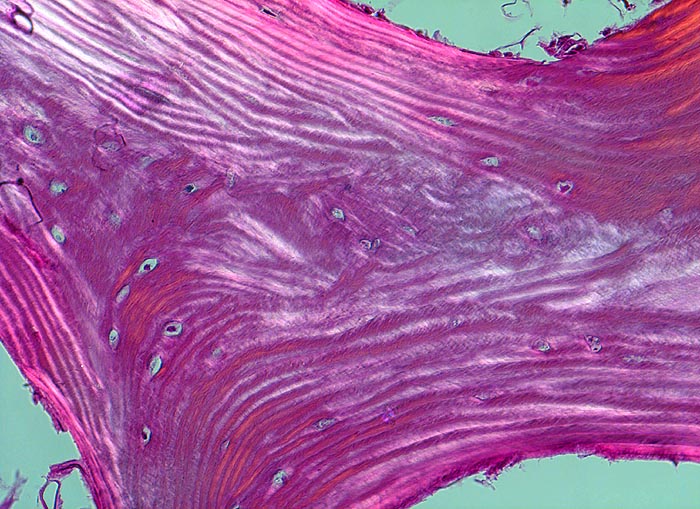

PathoPic ID 4511 - Normale Spongiosa

Normale Spongiosa

Normalbefund

Knochen, Tibia

Knochen, Knorpel, Gelenke

In der Doppelbrechung werden die regelmässig angeordneten Lamellen dieses Spongiosabälkchens besonders gut sichtbar.

Histologie

200